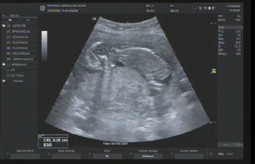

ซาวล่าสุด วันที่31-5-63

น้องน้ำหนักในครรภ์ 5.6 กรัม มากหรือน้อยค่ะ กังวลเล็กน้อย เพราะแม่แพ้ท้องหนักพอสมควร